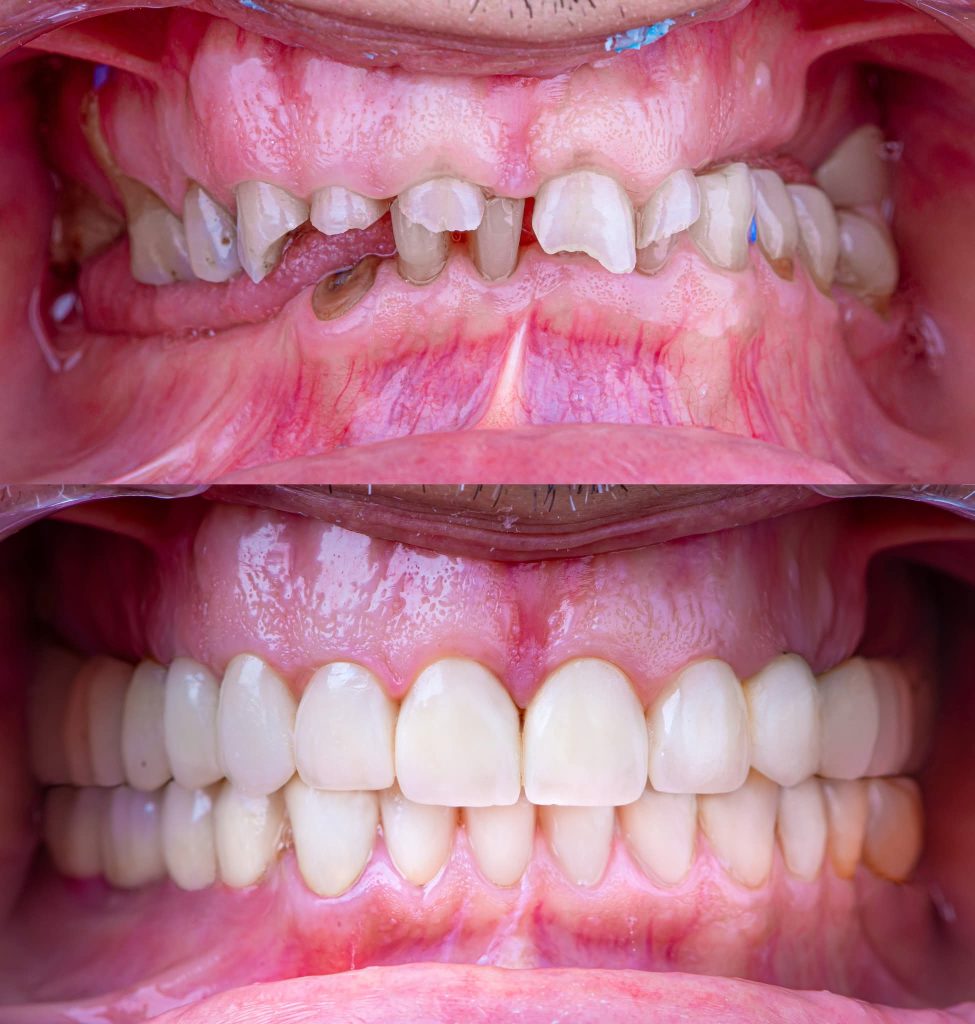

After almost 4 Years Follow-Up.

I am revisiting this Full Mouth Rehabilitation case, which was my first published case in this group.

Preparation of teeth and insertion of the fixed prosthesis.

The lower arch was managed similarly to the upper arch.

The patient has now been under follow-up for nearly 4 years and remains very happy and comfortable.